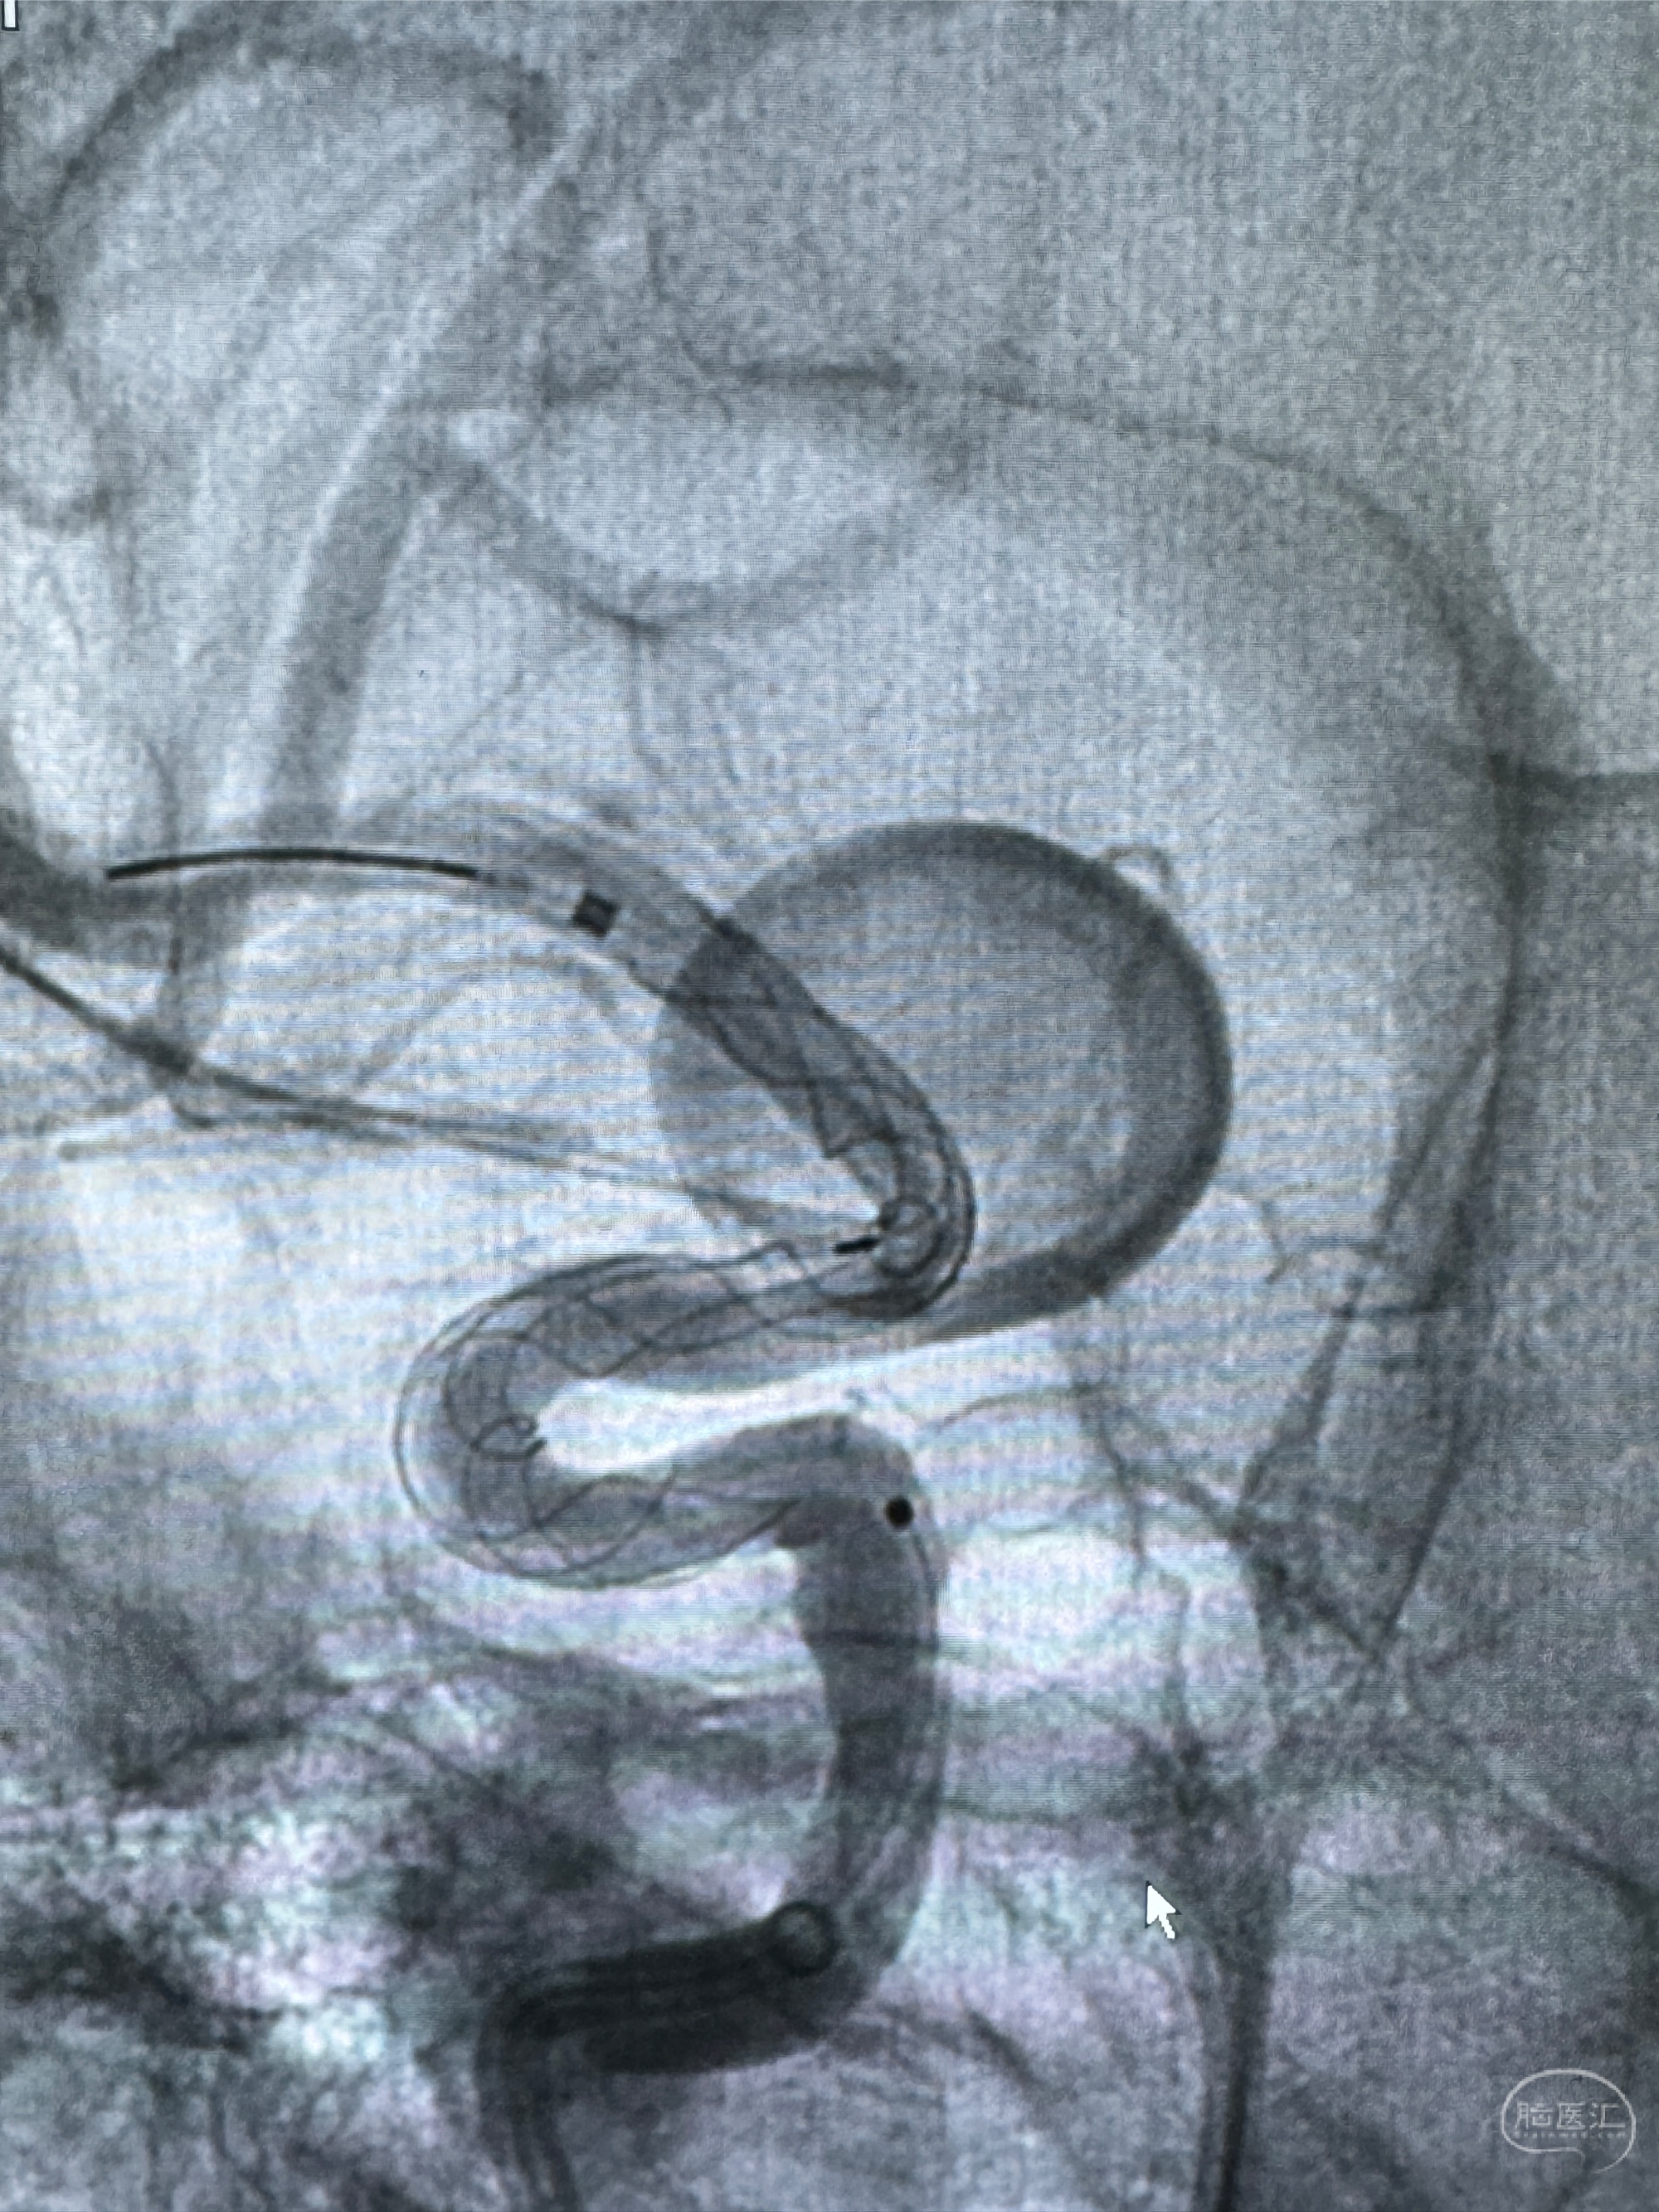

透视可见红圈部分为支架导管的头端

手推冒烟显示支架位置及展开情况,箭头为支架导管的位置

尝试回收支架失败,只能考虑释放支架了

逐帧图像展示歪着脖子释放支架,旁边吩咐助手手机摄影、拍照留像(透视机不能留影像)

接下的视频为释放支架的过程及试图确认支架与血管的关系